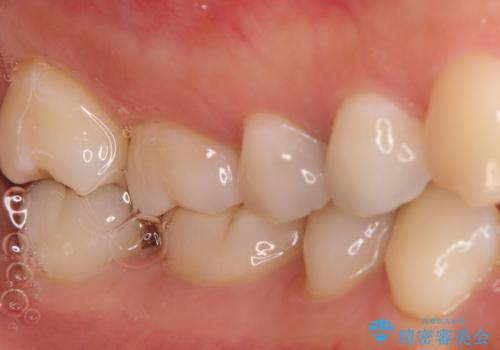

【セラミックインレー】むし歯の治療

- 定期検診にてむし歯を認めたため、セラミックインレーにて修復を行いました。

e-max プレスインレーにて修復治療を行っているため適合性及び審美性の高い治療を行うことができます